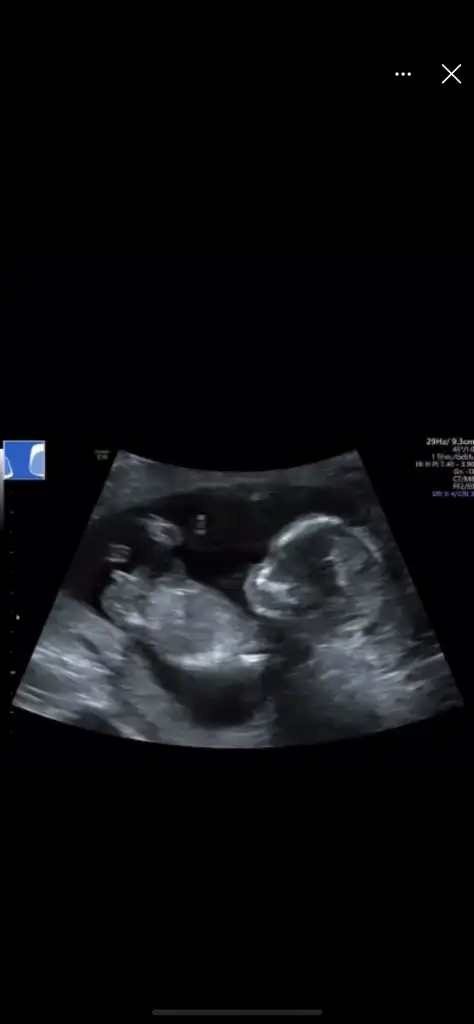

Kızlar merhaba karından ultrasonla bakıldı 10+6 cinsiyet tahmininiz nedir? 🤭 teşekkürler 🌸

• 18EE6BE5-7A40-45B3-9F6F-02162D0FD371.webp

18EE6BE5-7A40-45B3-9F6F-02162D0FD371.webp

11,7 KB · Görüntüleme: 67